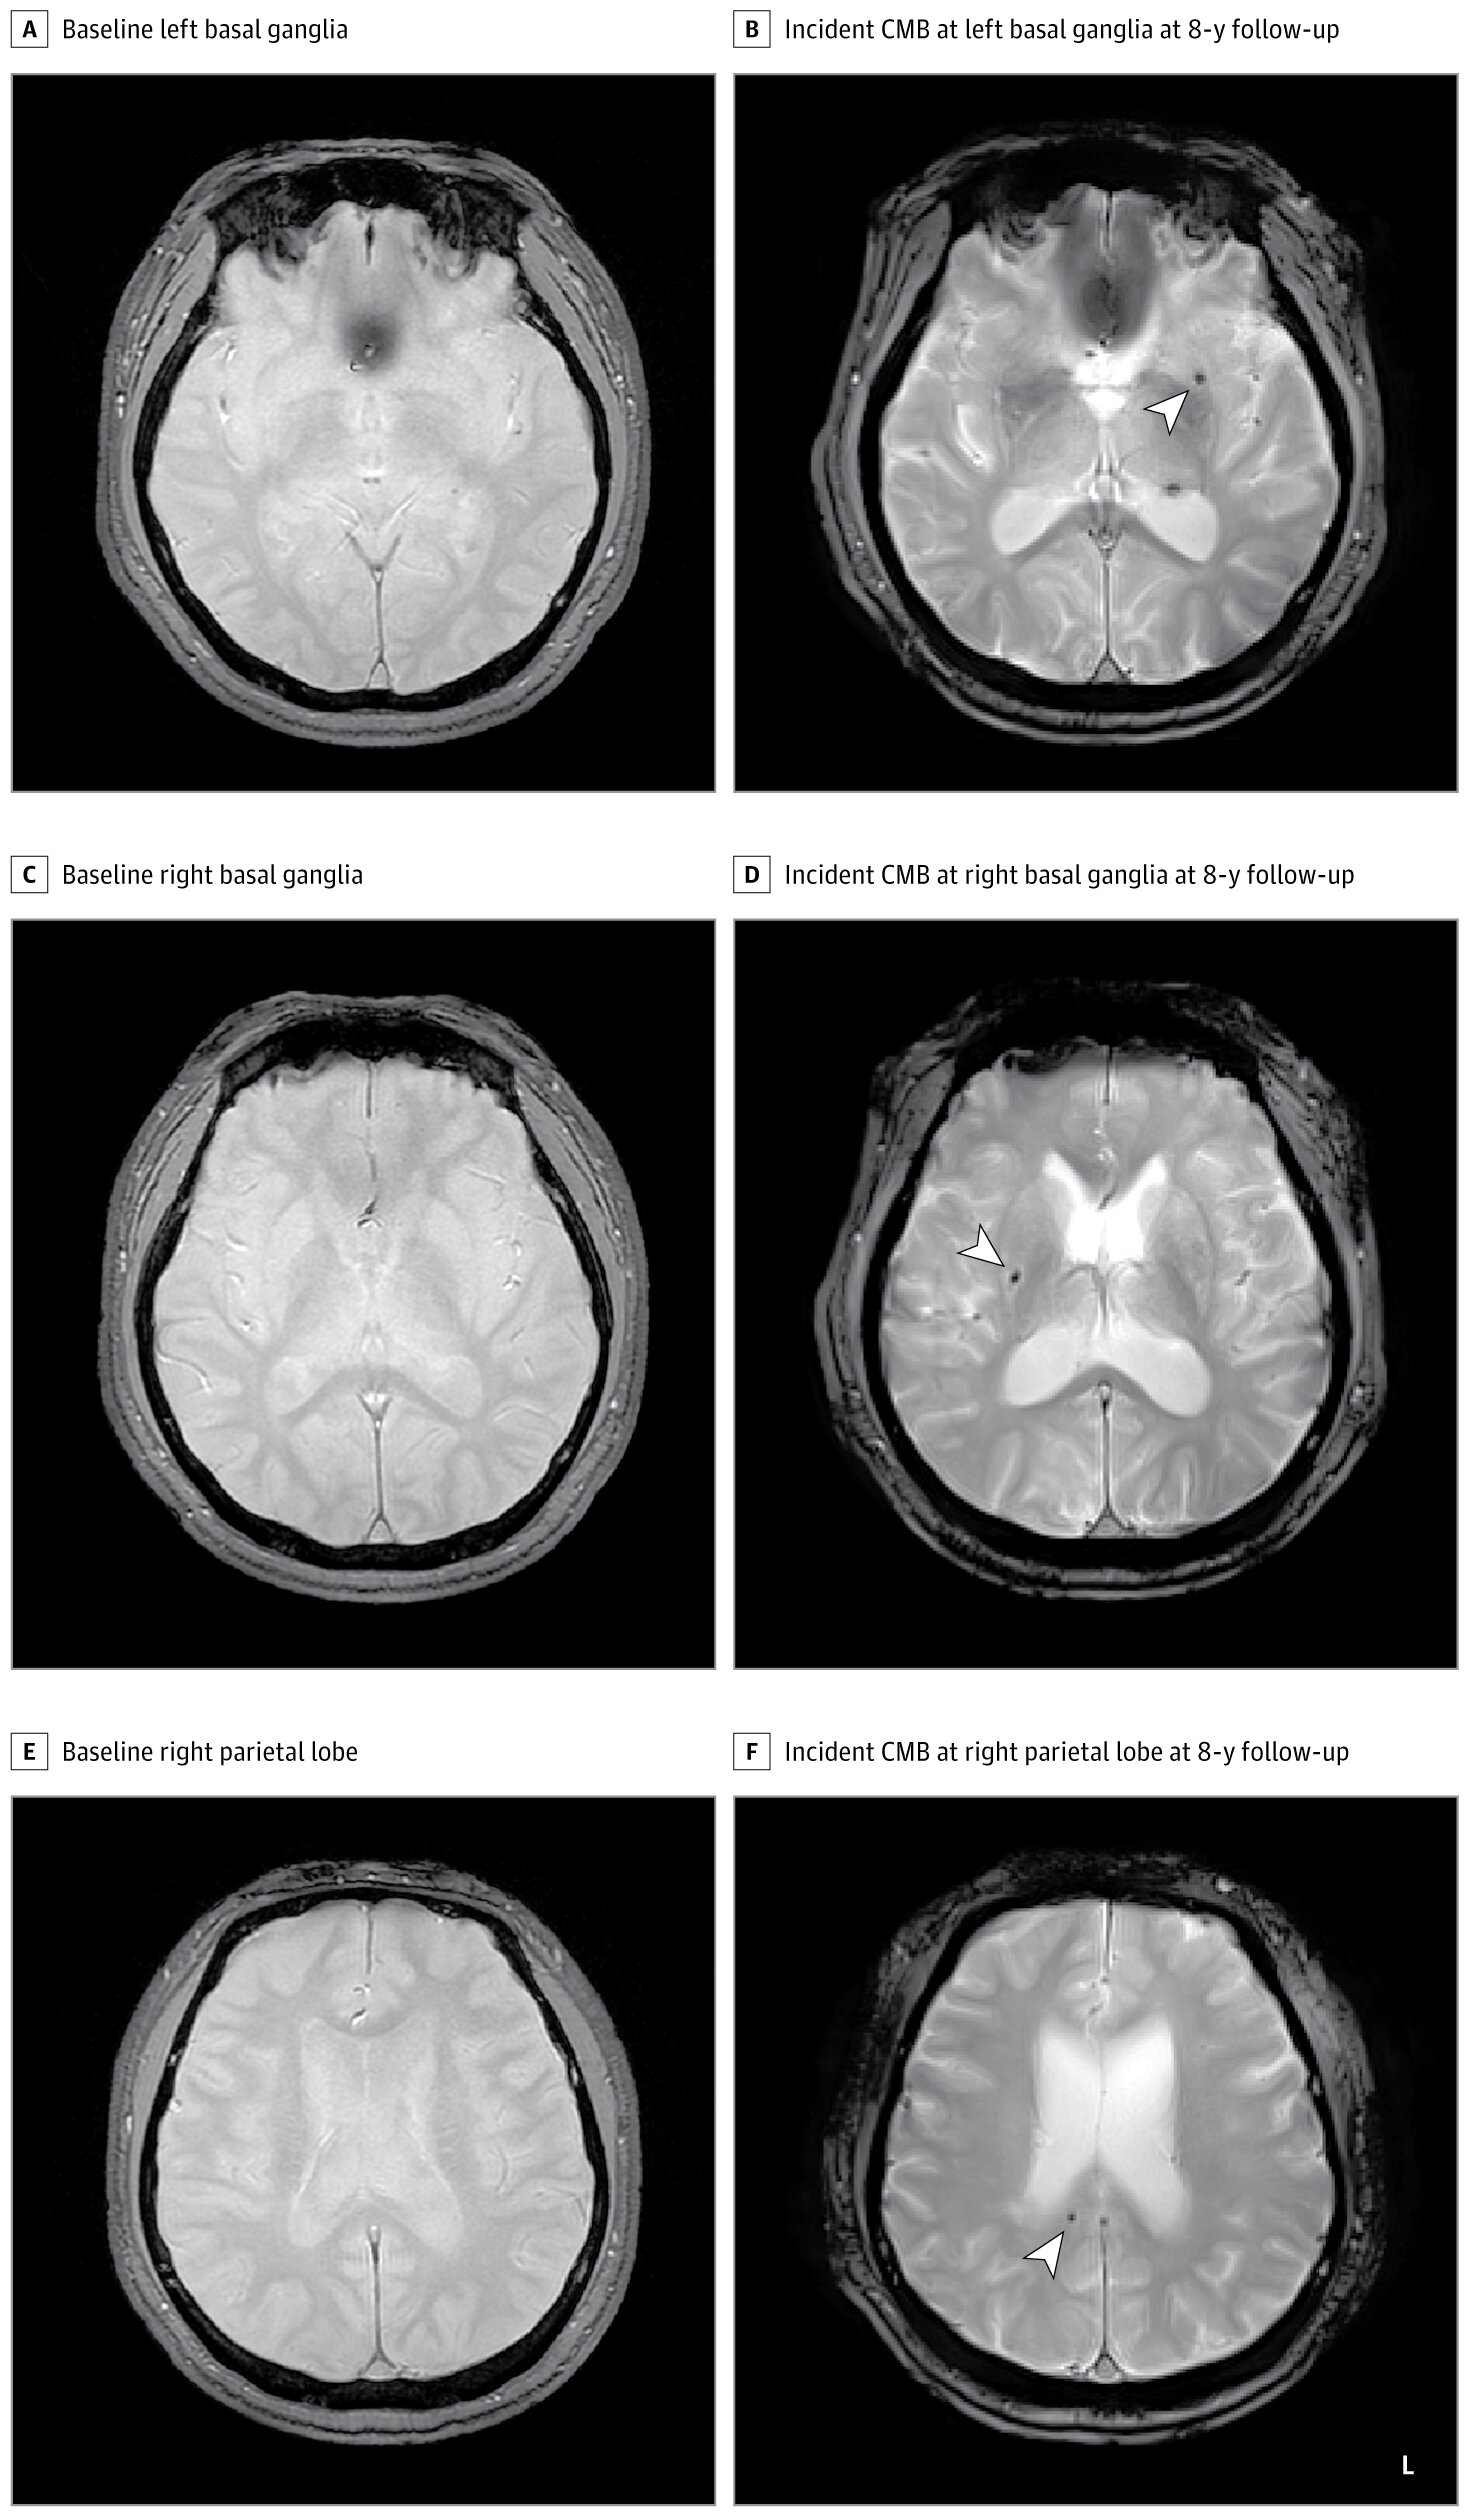

Cerebral microbleeds are minute spots of bleeding, often too small to cause immediate symptoms but large enough to be detected on high-resolution MRI scans. They appear as dark pinpoints—silent witnesses of vascular injury deep within the brain. For years, neurologists have recognized them as early markers of cerebrovascular fragility, linked to cognitive decline, stroke, and even Alzheimer’s disease.

The researchers followed 1,441 adults from a Korean community, all free of microbleeds or cardiovascular disease at the start. Each participant underwent in-home polysomnography—a comprehensive sleep test that tracks breathing, oxygen levels, and brain activity—alongside brain MRI scans. Over the following eight years, they were monitored for the development of new cerebral microbleeds.

At the four-year follow-up, microbleeds had developed in 1.85% of those without sleep apnea, 1.61% with mild apnea, and 4.66% with moderate to severe apnea. By eight years, those numbers grew to 3.33%, 3.21%, and a concerning 7.25%, respectively.

In simple terms, people with moderate to severe sleep apnea were more than twice as likely to develop cerebral microbleeds compared with those without the condition. Even after adjusting for known risk factors—such as smoking, high blood pressure, diabetes, and cholesterol—the association persisted.

The results paint a clear picture: the more severe the sleep apnea, the greater the likelihood of developing these early markers of brain injury.